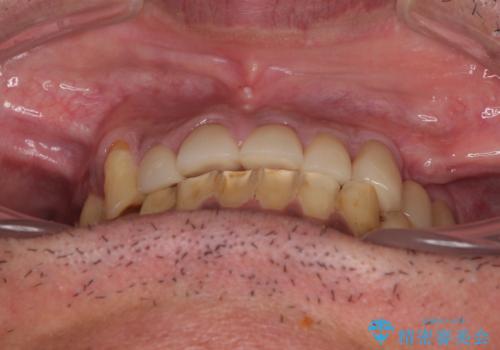

矯正治療は想定通り長期化しましたが、しっかりと奥歯の咬み合わせを向上させて前歯の被蓋を改善させることができました。

目立つ銀歯やすり減った前歯がセラミッククラウンとなり、患者様には大変満足していただけました。